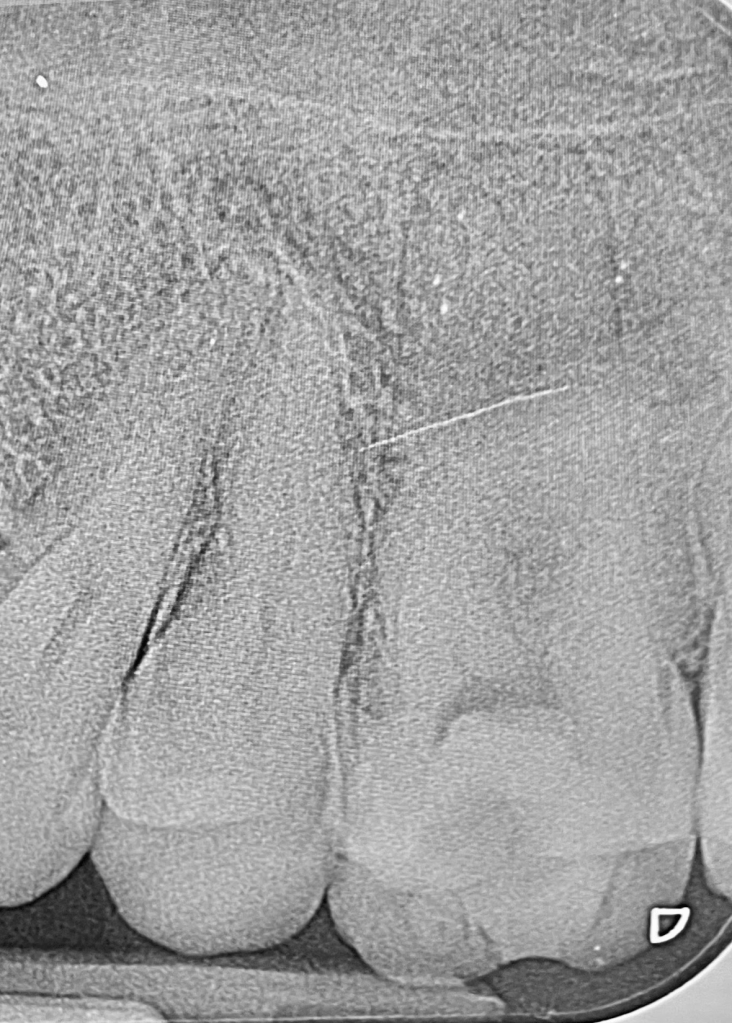

Incisivo inferior, trauma oclusal